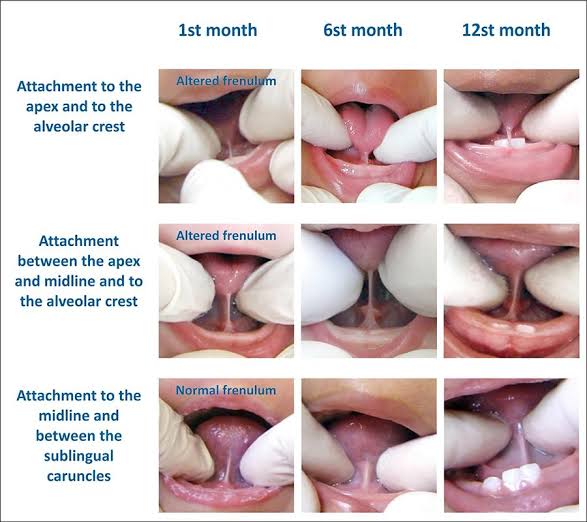

#Removal of Hypertrophic maxillary labial frenum:

In case of high frenum attachment ,where the frenum is not so close to crest of the ridge , surgery is not mandatory, only labial notch in the denture is sufficient. But when this notch breaks the peripheral seal , in that case surgical procedure is done.

#Removal of a Hypertrophic Lingual frenum:

Frenectomy is indicated in this case. Tongue tie test is performed.Patient is asked to touch his upper lip with tongue, if the denture is displaced by doing so then frenectomy is to be done.